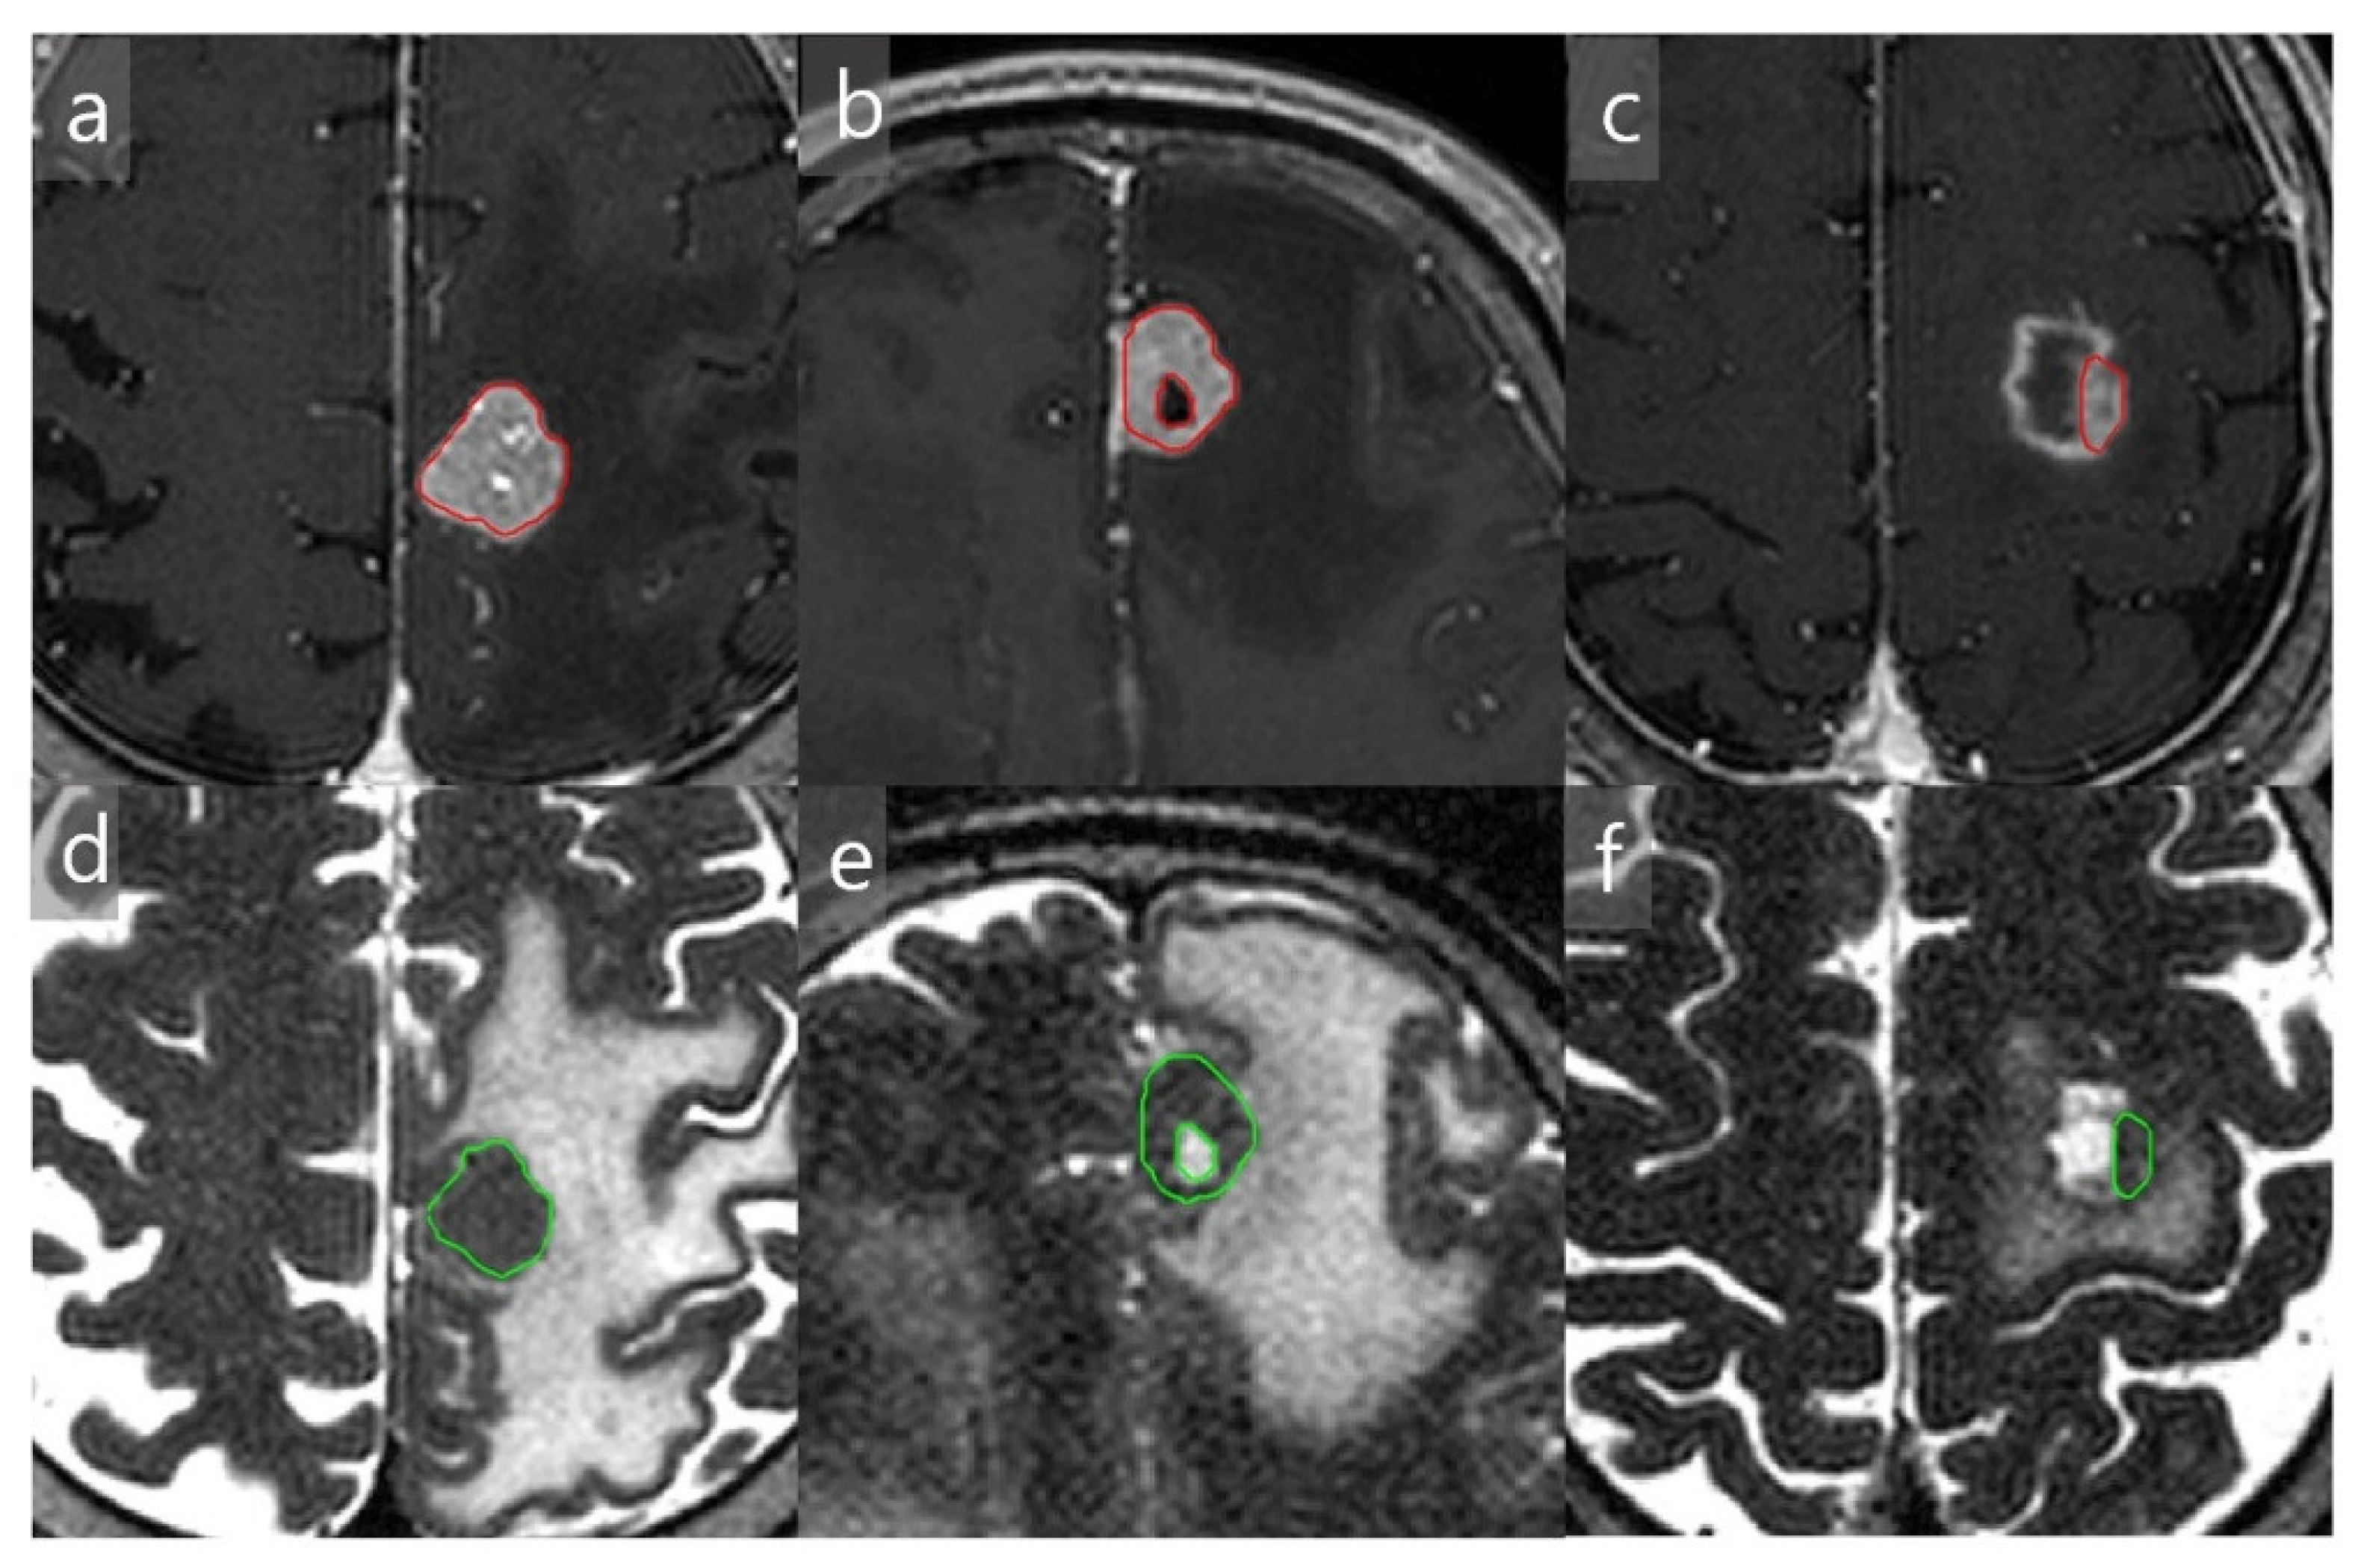

2.3.1. Tumor Identification, Characterization, and Region-of-Interest (ROI) Allocation